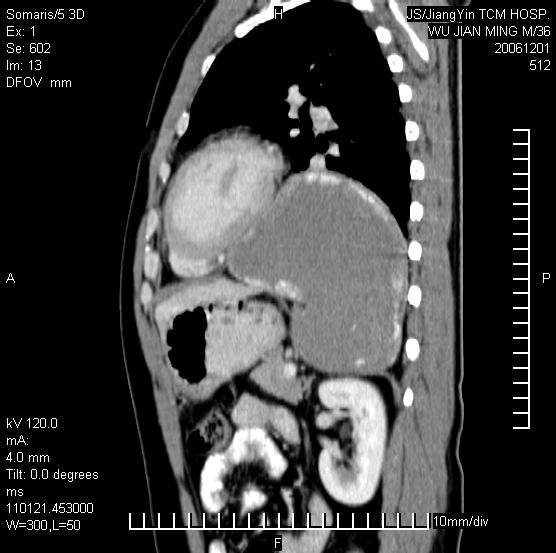

以下是引用dyqct在2006-12-1 21:17:00的发言:[br]左心缘旁及后肋膈窦区见巨大椭圆形混杂密度肿块,周围见大小不等斑片状钙化,内部无强化,周围包膜轻度强化,心脏明显受压变形,即明显占位效应,肿块广基与心包、膈相连。肝、脾内、肝门见多数小结节状钙化影。[br]考虑:1、左心缘旁及后肋膈窦区慢性包裹性胸膜炎(结核性);[br] 2、肝、脾及肝门淋巴结核已钙化。[br]

以下是引用zrs在2006-12-2 17:28:00的发言:[br]肺内、肝脾内虽有钙化,但不支持结核性胸胸膜炎包裹,而支持寄生虫感染![br][br]

以下是引用zyx168在2006-12-2 10:10:00的发言:[br][br]肝脾肺内多发钙化灶